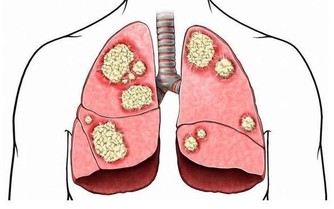

而當癌細胞進一步擴散,病情逐漸惡化時,會影響到消化系統以外的部分。

例如患者的糞便會參有血跡,體重也異常減輕,時常感到疲倦乏力,由於胃部有積液還會引起胃脹胃痛;

嚴重時還會導致貧血和呼吸困難,皮膚和眼白也會開始泛黃。